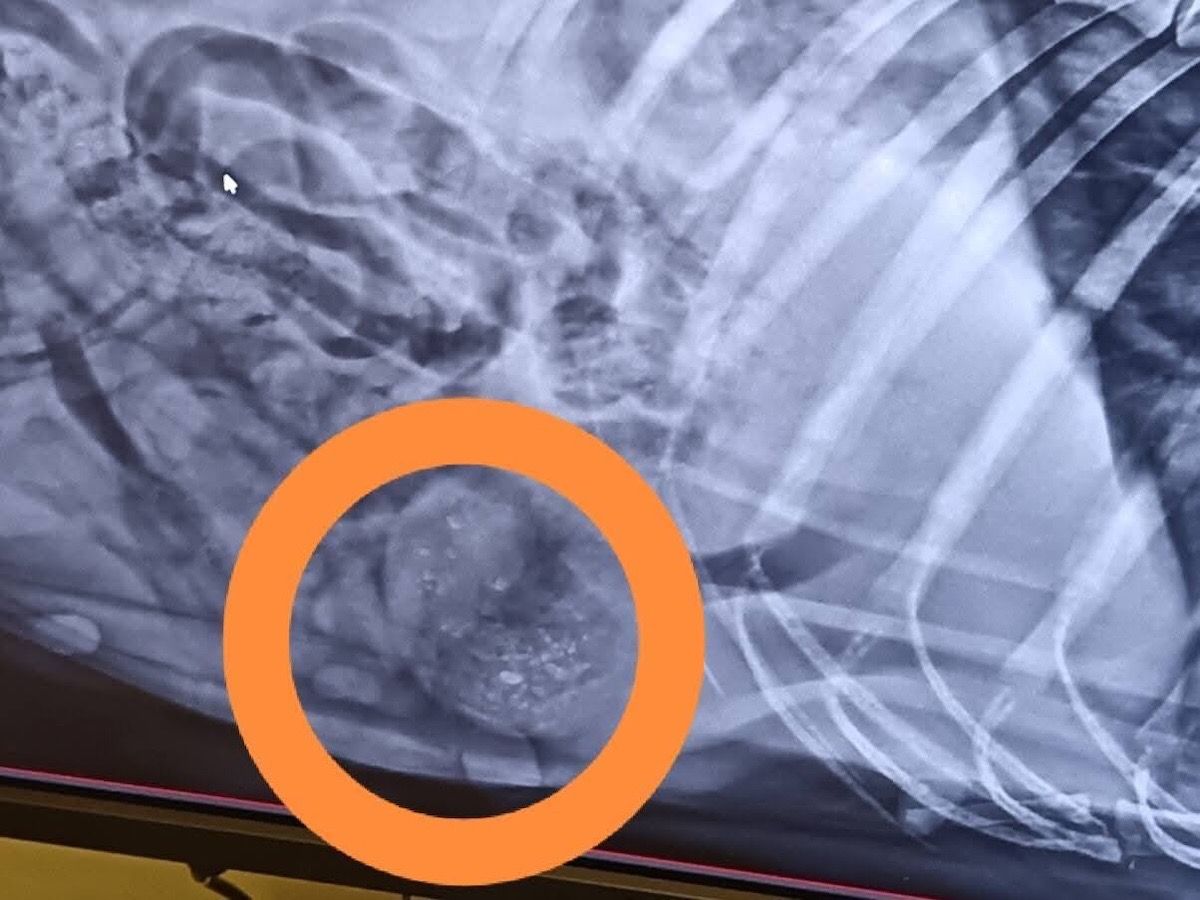

Anett hat uns heute über den aktuellen Gesundheitszustand von Mama Katica berichtet – leider mit überwiegend schlechten Nachrichten. Katica hat einen großen Weichteilbruch auf der linken Seite. Ihre Gesäugeleisten sind von kleinen Tumoren übersät.

In ihrem Bauch befinden sich Luftgewehrgeschosse.

Es wurden ein Bauchultraschall, Röntgenaufnahmen und Blutuntersuchungen durchgeführt – zum Glück waren alle Testergebnisse negativ. Der Ultraschall ergab zudem, dass sie kürzlich geworfen hat – ihre Gebärmutter ist noch offen.